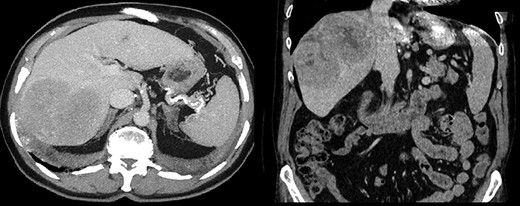

A 64-year-old male with severe ischemic cardiomyopathy underwent implantation of an LVAD (Heart mate II™, Abbott, Chicago, USA) in 2012. Decision of LVAD as destination therapy instead of heart transplantation was made due to history of hepatitis B infection, chronic kidney insufficiency and COPD. Patient remained in good condition with normal LVAD function. Further history included atrial fibrillation and pulmonary embolism. In 2019, hepatocellular carcinoma (HCC) was incidentally detected in the postero-lateral sector of the liver. Preoperative LiMax-Test [2] revealed good liver function (316 μ/kg/h), MELD XI Score was 15 without signs of portal hypertension. Staging revealed no distant metastases and confirmed local resectability (comp. Fig. 1).